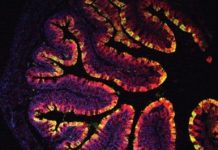

Research: Chemicals found in vegetables prevent colon cancer in mice —

Chemicals produced by vegetables such as kale, cabbage and broccoli could help to maintain a healthy gut and prevent colon cancer, a new...